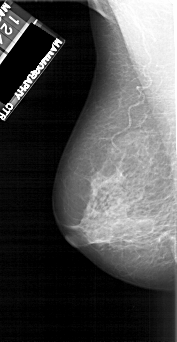

LEFT_MLO LINES 5116 PIXELS_PER_LINE 2641 BITS_PER_PIXEL 12 RESOLUTION 43.5 NON_OVERLAY